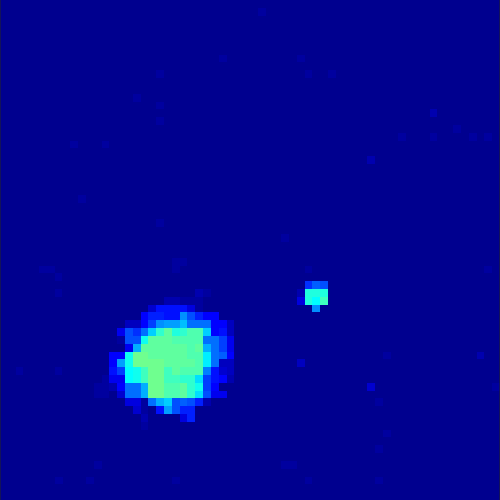

In two different tests we fixed the number of events counted by the detector equal to (resp. ) times the average concentration in one pixel. The resulting sinogram images of the accumulated counts in each bin are shown in figure 9.

Based on the sinogram data we applied the proposed algorithm in order to reconstruct the original image sequence. The results for both test cases are shown in figure 10.

As one can see, the method is able to reconstruct the regions properly, even in case of a low count number. Within a number of iterations (average of 100 outer and 10000 inner iterations), the algorithm presents a reasonable reconstruction of the region of interest and the corresponding regional tracer concentration curves. Here, the parameters were not optimized as in the case of the synthesized data sets in the previous section, but kept fixed as , and . With futher optimized parameter values one could possibly provide even better results.